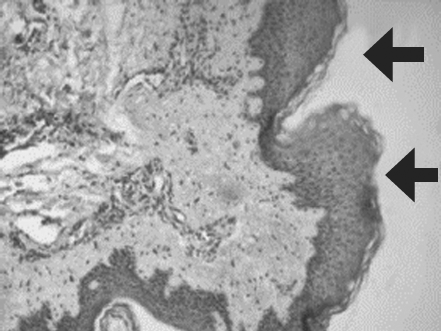

Histological examination of biopsy samples taken from the area of ATMSC transplantation for all the patients revealed the presence of pronounced vascularization with the perifocal proliferation of fibroblasts in both the superficial and deep layers of the dermis (Fig. 6, 7). An immunohistochemical study revealed that the use of ATMSCs resulted in a 5.6-fold increase in the expression of proliferation markers of epithelial and connective tissue cell lines in the injection area (p < 0.01) (proliferation 2.1–2.2), and that apoptotic activity was completely suppressed (Fig. 8, 9). Laser Doppler flowmetry assessment of the microcirculation in the area of stem cell injection on day 7 after early necrectomy, skin grafting, and the administration of MMSCTM showed double the average level of perfusion and mean square deviation of the amplitude of blood flow oscillations than for areas where MMSCTM was not used (p < 0.05) (Table 6).

Fig. 9. Patient E., 49 years old. Significant expression of the proliferation marker of Ki 67 cells of an autologous cutaneous graft on the 5th day after the AMSC injection. Zoom ×600

Рис. 9. Пациент Д., 49 лет. Выраженная экспрессия маркера пролиферации Ki-67 клетками аутологичного кожного трансплантата на 5-е сутки после введения мезенхимальных стволовых клеток жировой ткани. Увеличение ×600